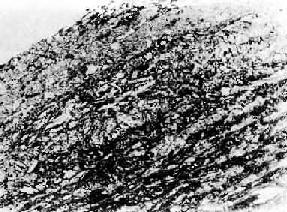

发展中的纤维粥样斑块

图8-5 发展中的纤维粥样斑块

图8-4的斑块深层。高倍镜下可见大量胆固醇结晶、泡沫细胞和增生的平滑肌细胞